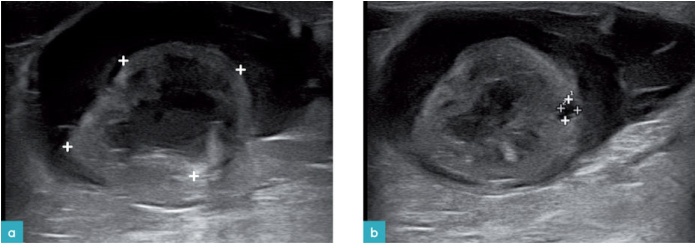

肾周假性囊肿通常发生在较老的猫中,并且可能伴随CKD病变;手术或导致静脉充血的肿瘤也会引发肾周假性囊肿。在超声波上,肾周假性囊肿表现为肾小囊和实质之间无回声的液体积聚,并且可能影响一侧或两侧肾脏。超声波显示存在一个无回声和囊状结构。肾脏倾向于占据偏心位置,并具有改变的回声结构,皮髓质界定不强以及存在强回声的皮质(图37.视频19)。